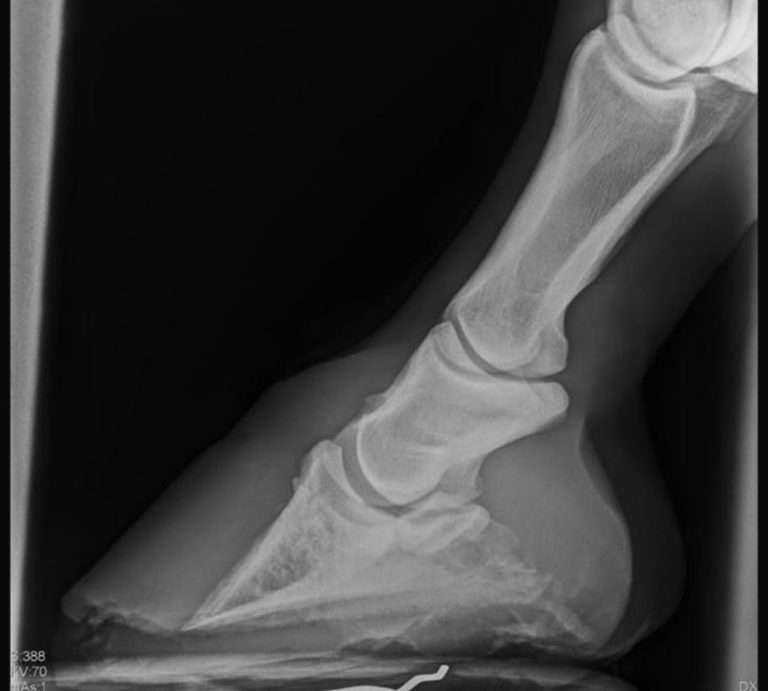

2-3 Tage Intensiv Workshop mit Beschlagsmöglichkeiten von Erkrankungen der distalen Gliedmaße und vor Ort Röntgen

z.B. Hufrehe, Hufrollenerkrankungen, Negative Palmare Hufbeinwinkel, Fehlstellungen & Mediolaterale Imbalancen